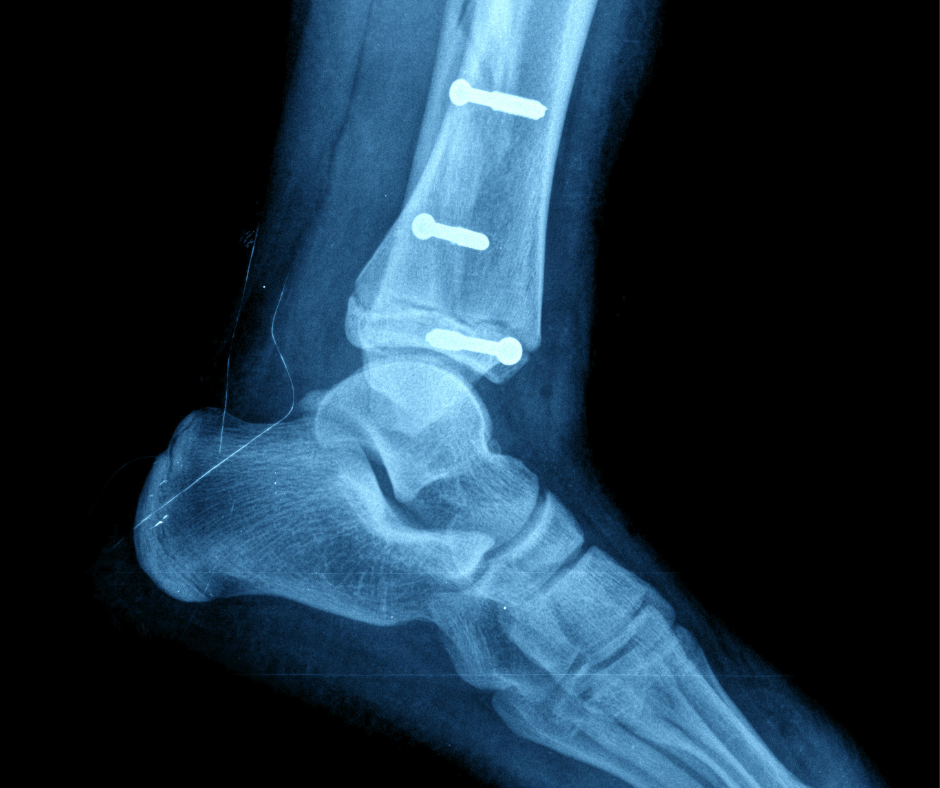

Surgical Screws: Supporting Healing and Ensuring Stability

- Stabilizing Fractures: During surgery to correct foot fractures, screws are meticulously inserted into broken bones to hold them firmly in place.

- This stability is key for proper healing, preventing displacement of the fragments throughout the process.

- Screws act as an internal support system, promoting optimal recovery for damaged bones.

- Securing Implants: Screws play a vital role in securing implants like plates, rods, and artificial joints to bones in foot surgery.

- They create a stable connection between the implant and the bone, thanks to their structural rigidity.

- This helps prevent implant movement and promotes optimal recovery.